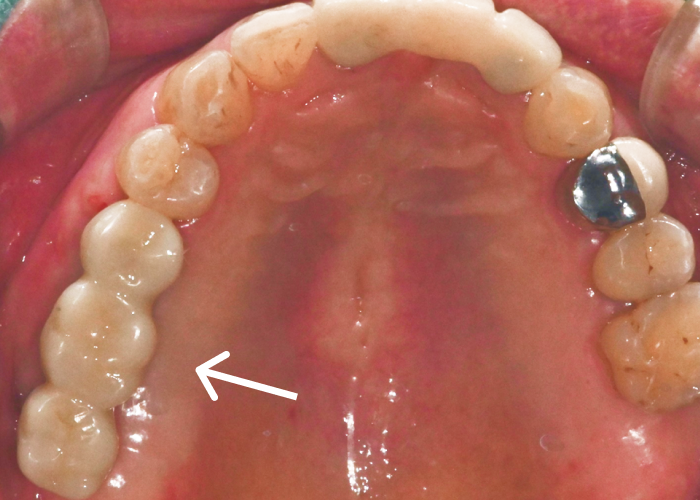

맞춤형 어버트먼트를

체결한 모습입니다.

환자 개개인의 잇몸 형태와 뼈 높이는

모두 다르기 때문에,

기성 어버트먼트를 사용하면

보철물과 잇몸 사이에

미세한 틈이나 단차가 생기기 쉽습니다.

이 틈은 시간이 지나면서

음식물 저류나

세멘트 잔여물 축적을 유발하여

염증으로 이어질 수 있습니다.

맞춤형 어버트먼트는

디지털 스캔 데이터를 기반으로

잇몸 곡선을 그대로 반영해 제작되므로,

보철물이 올라갔을 때

잇몸과 자연스럽게 이어지고

위생 관리도 수월합니다.